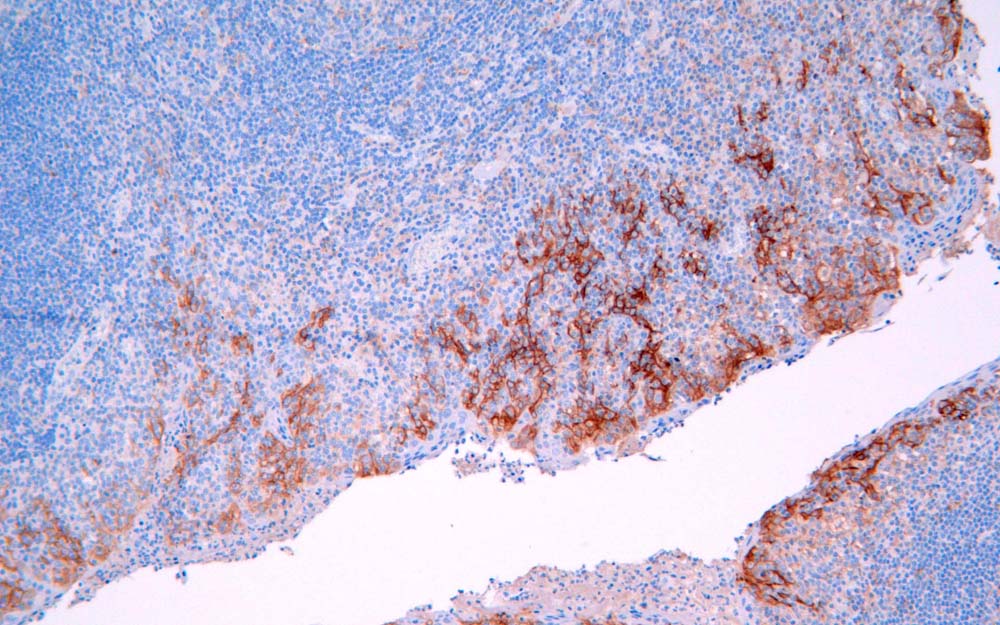

IHC (Immunohistochemisry)

(Immunohistochemical analysis of paraffin-embedded human tonsil tissue. Tissue was fixed with formaldehyde at room temperature, antigen retrieval was by heat mediation with a EDTA buffer (pH9. 0). Samples were incubated with primary antibody for 15 min at room temperature. Secondary: Goat Anti-Rabbit IgG (H&L))